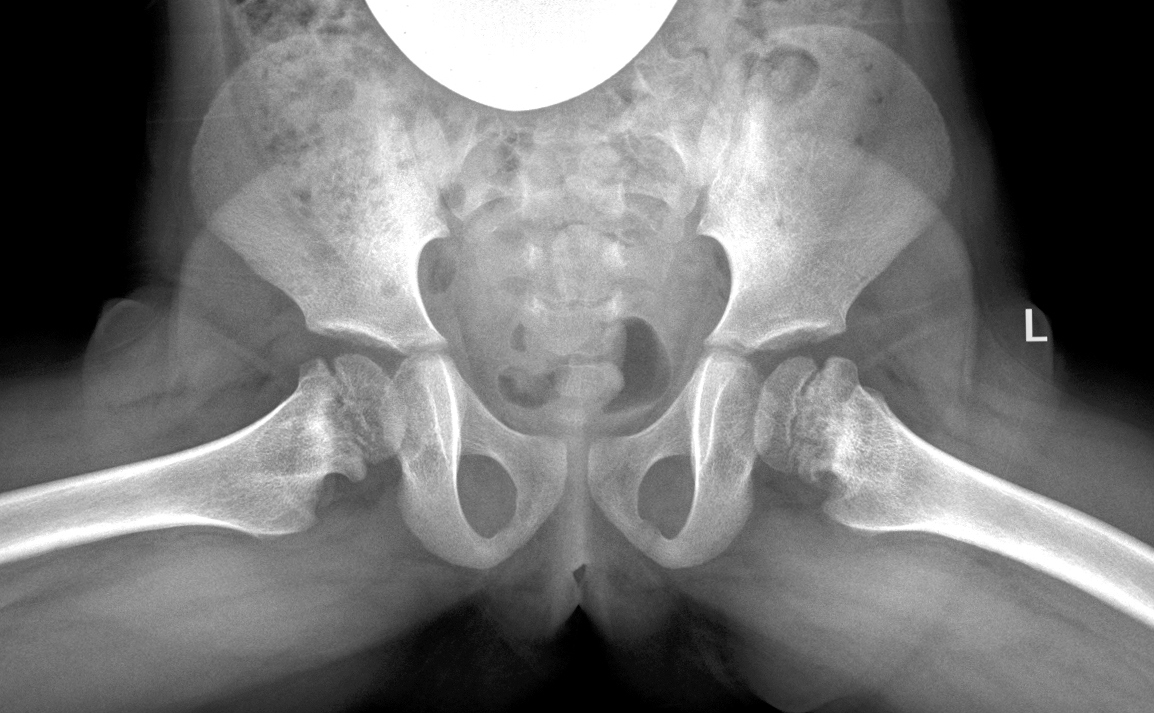

У всех 350 наблюдаемых пациентов показатель отношения верхушки большого вертела к центру головки бедренной кости принимал патологические значения, что служило основным критерием включения в исследование. Для подробного анализа происходящих анатомических изменений мы изучили дополнительные показатели, характеризующие соотношения головки бедра и большого вертела во фронтальной плоскости у 56 обследованных пациентов (112 тазобедренных суставов). Из них развитие 48 (42,9 %) суставов было нормальным (при одностороннем поражении) (рис. 1).

Рис. 1. Показатели, характеризующие соотношения головки бедра и большого вертела во фронтальной плоскости (McCarthy J.J., Weiner D.S., 2008, с изменениями) [12]. ATD — артикуло-трохантерная дистанция; TTD — межвертельное расстояние; LTA — расстояние от малого вертела до верхнего полюса головки бедра

а) артикуло-трохантерная дистанция (articulo-trochanteric distance, ATD) — расстояние от верхушки большого вертела до верхнего полюса головки бедра (мм);

б) межвертельное расстояние (trochanter-to-trochanter distance, TTD) — расстояние от верхушки большого вертела до середины малого вертела вдоль линии, параллельной анатомической оси бедренной кости. Показатель отражает рост большого вертела и не зависит от роста эпифиза;

в) расстояние от малого вертела до верхнего полюса головки бедра (lesser trochanter-to-articular surface distance, LTA). Показатель отражает рост эпифиза и шейки бедренной кости и не зависит от роста большого вертела.